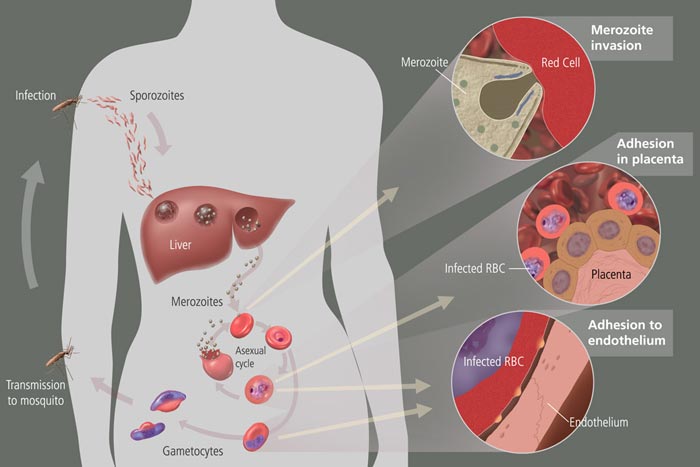

Life cycle of malaria.NIH via <a href="http://commons.wikimedia.org/wiki/File:MalariacycleBig.jpg">Wikimedia Commons</a>.

Being born with immunity to the diseases prevalent in your ‘hood because you inherited the antibodies from your mother (who suffered and survived the disease) is an important factor in human survival and adaptability This is especially true in places where you’re likely to be reinfected with the same disease/parasite multiple times in your lifetime.

But what happens if you treat the mother for the infection? Will her children inherit maternal immunity? The evidence remains inconclusive as to whether treating human moms for malaria improves the survival rate of their kids. But a new study in mice shows: not so much.

The paper in Proceedings of the Royal Society B finds that:

- Baby mice born to moms who had been infected by malaria had their mortality reduced by 75 percent compared to babies born to moms who had never been infected with malaria and had no antibodies to confer.

- Baby mice born to infected moms treated with antimalarial drugs received fewer maternal antibodies and consequently died at a rate 25 percent higher than babies born from infected, untreated moms.

We observed the same qualitative patterns across three different host strains and two parasite genotypes. This study…highlights a potential trade-off between the health of mothers and offspring, suggesting that anti-parasite treatment may significantly affect the outcome of infection in newborns.